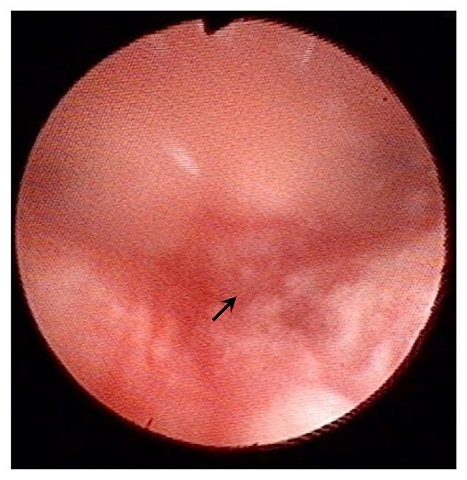

【子宮內膜刺激術是在子宮內視鏡下,在子宮後壁特定區域輕刮幾個傷口。】

(作者蔡鋒博提供照片)